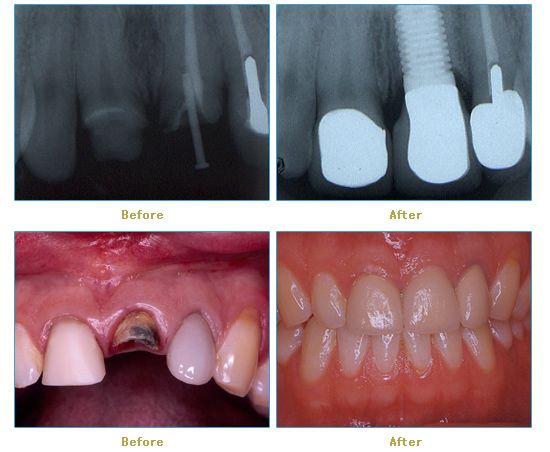

Dr. Cabianca has restored hundreds of smiles through the latest techniques in restorative and cosmetic dentistry. The following before and after photos document a few such cases in which Dr. Cabianca has replaced and reshaped teeth to produce wonderful smiles. Click on any of the images below to view larger versions of the photos.